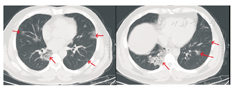

患者男,47岁,黑龙江省哈尔滨市人。因"发热5 d"于2020年1月21日收入我院发热留观病房。既往健康,否认慢性病史及传染病史。患者为火车司机,往返于哈尔滨——武汉区间。发病前两周曾两次随车到达武汉,并在武汉火车站站台逗留。2020年1月16日开始出现发热,体温在37.5~39 ℃,伴畏寒,无寒战。无咳嗽及咯痰,无喘息及呼吸困难。入院前1 d曾有轻微腹泻症状,排稀便两次,未见脓血。入院后查体:一般状态尚可,呼吸平稳,体温38.2 ℃,脉搏108次/min,呼吸16次/min,血压140/95 mmHg(1 mmHg=0.133 kPa)。球结膜轻度充血,双肺听诊呼吸音清,未闻及干湿啰音。入院当日在我院发热门诊行血常规检查:白细胞(WBC)6.14×109/L,中性粒细胞占比0.560,淋巴细胞占比0.337,淋巴细胞绝对计数2.07×109/L,单核细胞占比0.103,红细胞及血小板计数正常。胸部CT:左肺及右肺上下叶可见斑片影,边界模糊。影像学诊断:左肺及右肺上下叶炎性改变(图1)。入院当日市疾控中心行咽拭子2019-nCoV核酸检测阴性,其他相关检查结果:C-反应蛋白16.8 mg/L(参考值0~8 mg/L),红细胞沉降率38.00 mm/1 h(参考值0~15 mm/1 h),降钙素原0.10 ng/mL(参考值0~0.046 ng/mL),肌红蛋白203 ng/mL(参考值0~154.9 ng/mL),肌酸激酶1 149.60 U/L(参考值38~174 U/L),G-脂多糖、肝肾功能、凝血功能正常。相关病原学检查:甲型流感病毒、乙型流感病毒、副流感病毒-2型、嗜肺军团菌、肺炎支原体、肺炎衣原体、Q热立克次体、腺病毒、呼吸道合胞病毒、风疹病毒、单纯疱疹病毒、巨细胞病毒、弓形虫IgM抗体均阴性。EBV DNA定量<5.0×102拷贝/mL。入院当日开始静脉点滴盐酸莫西沙星氯化钠注射液(0.4 g/d),口服磷酸奥司他韦胶囊(75 mg/次,2次/d),补液对症治疗。1月23日,患者仍有间断高热,体温可达40 ℃。偶有轻微干咳,无痰。市疾控中心第2次咽拭子2019-nCoV核酸检测仍为阴性,我院复查血常规:WBC 4.89×109/L,中性粒细胞占比0.583,淋巴细胞占比0.319,淋巴细胞绝对计数1.56×109/L,单核细胞占比0.098。胸部CT:双肺可见斑片影及磨玻璃影,边界模糊。影像学诊断:双肺炎性改变(图2)。咽拭子细菌培养、血细菌+真菌培养未检出病原体。继续给予上述药物治疗,同时行物理降温,未应用退热药物。因两次2019-nCoV核酸检测阴性,建议患者回家中自行隔离治疗。1月24日患者仍有发热,咳嗽频繁,咯白痰,且患者配偶亦出现发热症状,即到我院急诊内科留观隔离,继续予盐酸莫西沙星氯化钠注射液静脉点滴、口服磷酸奥司他韦胶囊(两种药物剂量同上)。1月26日患者仍发热,体温最高达38.5 ℃,自觉胸闷、呼吸急促,查动脉血气分析:PaO2/FiO2:342 mmHg。血常规:WBC 4.37×109/L,中性粒细胞占比0.687,淋巴细胞占比0.197,淋巴细胞绝对计数0.86×109/L,单核细胞占比0.115。胸部CT:双肺可见淡片影,磨玻璃影,范围较前扩大,边界不清。影像学诊断:双肺炎症(图3)。1月27日我院组织院内专家会诊,认为该患者虽然两次2019-nCoV核酸检测阴性,但结合流行病学史及临床表现(高热,淋巴细胞计数进行性减少、肺部间质性病变且进行性加重),不能排除2019-nCoV感染,申请市疾控中心行第3次咽拭子2019-nCoV核酸检测,结果仍为阴性。患者仍维持原治疗方案治疗。1月28日患者体温趋于正常,自行离院,在家中继续隔离治疗。每3日对患者进行电话随访,患者未再出现发热,咳嗽、咯痰明显缓解,未出现呼吸困难。因疫情期间特殊情况,未到我院进行相关复查。